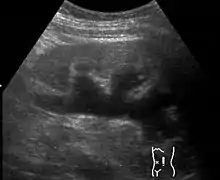

Renal ultrasonography of hydronephrosis caused by a left ureteral stone.